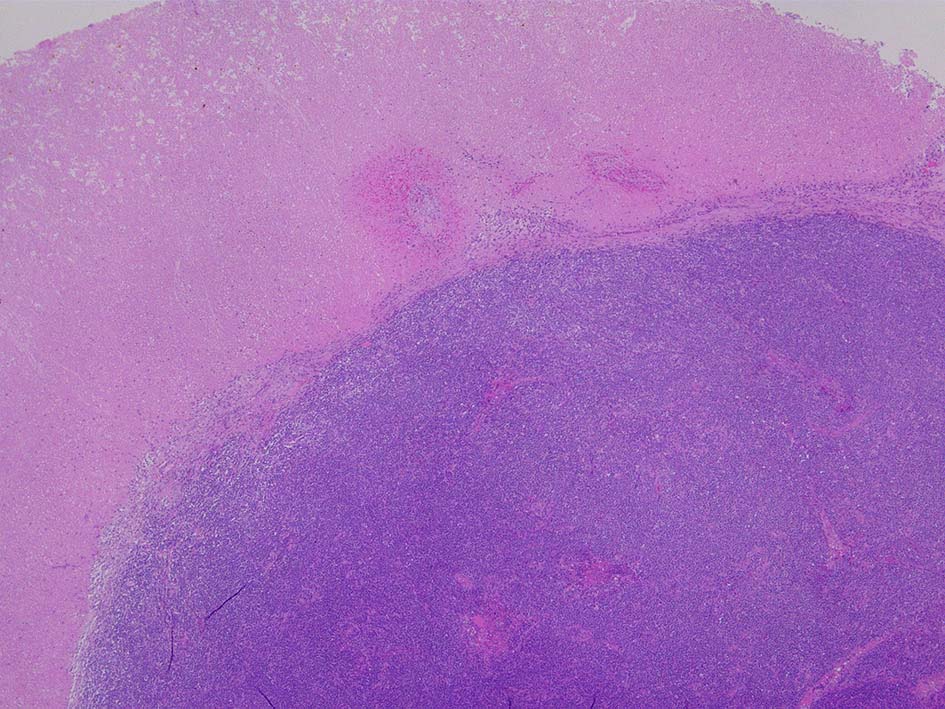

腫瘍内に壊死が認められる. 異型リンパ球の密な増殖により精細管は消失している.

腫瘍細胞はcentroblastic cells. mitosisやapoptosisが多い.

Diffuse large B-cell lymphoma of the lt. testis, 6.0x5.0x4.5cm in size.